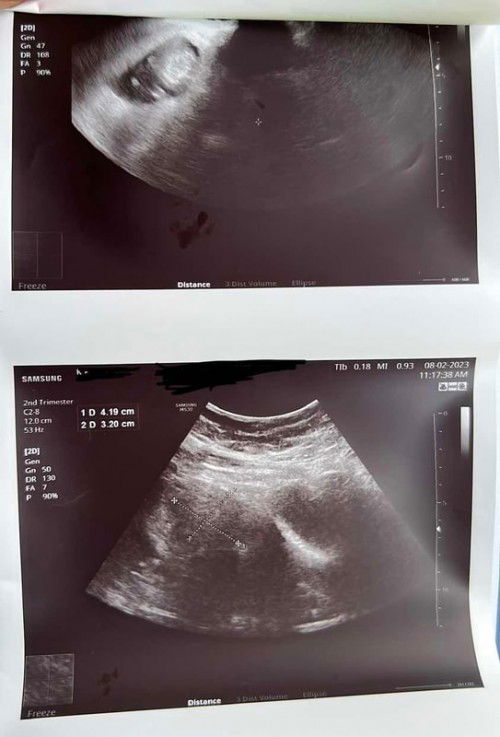

Ada Fibroid Dan Air Ketuban Kurang Diusia Kandungan 12weeks 3Days

Hai mommies, sekadar nak berkongsi pengalaman jika ada diantara ibu2 hamil disini yg pernah mengalami situasi seperti saya. Boleh sharing2 tak? Doktor di KK dah booking date utk saya berjumpa dgn doktor pakar berkenaan dgn masalah yg sy hadapi, cuma sy nak tahu jika ada ibu2 yg senasib seperti sy dan jika ada petua yg boleh dikongsikan bersama, jasa baik ibu2 semua sgt2 sy hargai 🙏🏻 Sebagai info : gambar atas adalah gambar scan baby, dan gambar bawah adalah gambar ukuran fibroid. #advicepls #pleasehelp #ingintahu